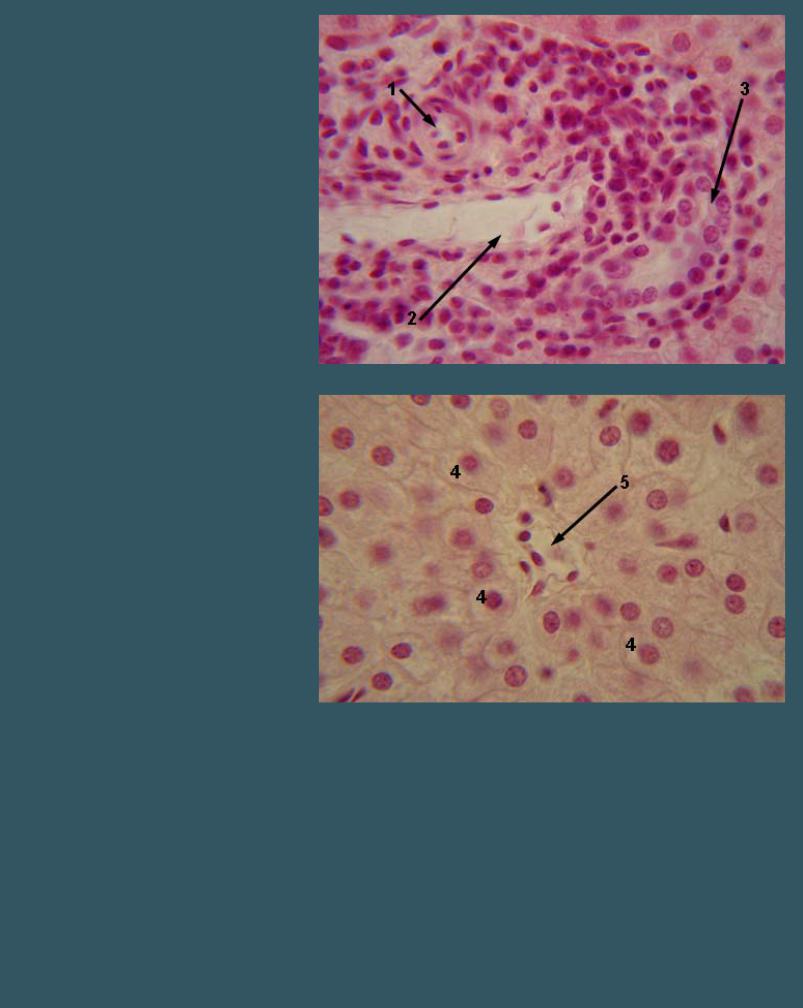

ПЕЧЕНЬ

Окраска гематоксилин-эозином

4 - гепатоциты

5 - центральная вена

ПЕЧЕНЬ

Окраска гематоксилин-эозином

4 - гепатоциты

5 - центральная вена

6 - внутридольковый синусоидный капилляр